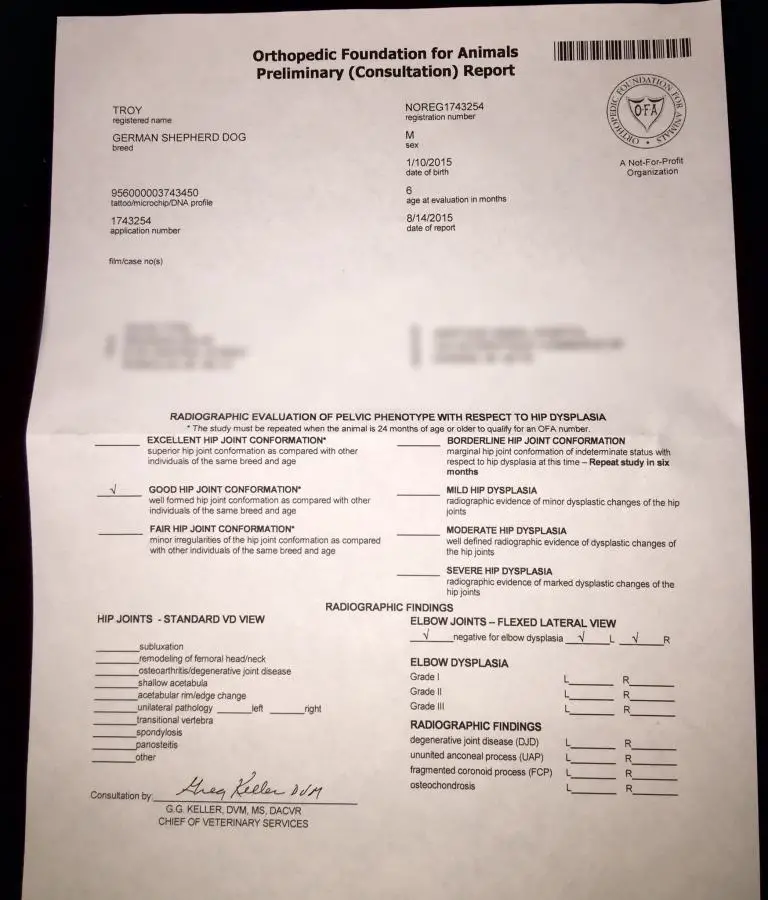

PRELIMS.

This is one of the best positioned hip xrays we've ever seen on this forum. Your vet did a really great job.

Some members on the German Shepherd forum said his hips weren't properly postponed. Thoughts?

Whoever said that was wrong, cholster. They could not be any better.